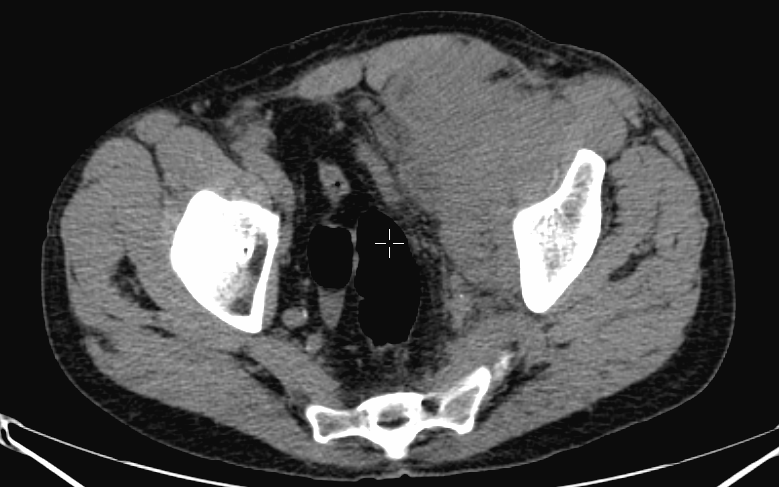

The most common indication of bone scintigraphy is the evaluation of bone metastasis. (Figure 5.)

Image

a

b

c

d

5. Multiplex bone metastases. Bone scintigraphy, anterior (a) and posterior (b) whole body scans. SPECT-CT sagittal plane, fusion image (c) and CT image (d). Obvious bone structural changes cannot be identified on the CT scan yet.